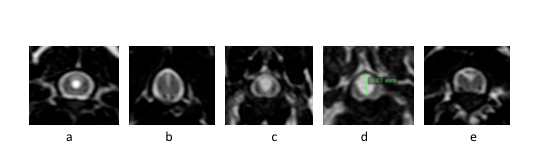

• Dwarsdoornedes van het ruggenmerg (T2 beelden). Diverse vormen van syringomyelie: a circulaire verwijding, b verwijding naar boven, c ernstigere variant van b, d zeer ernstige variant (er is nog maar nauwelijks ruggenmerg) en e verwijding naar opzij.*